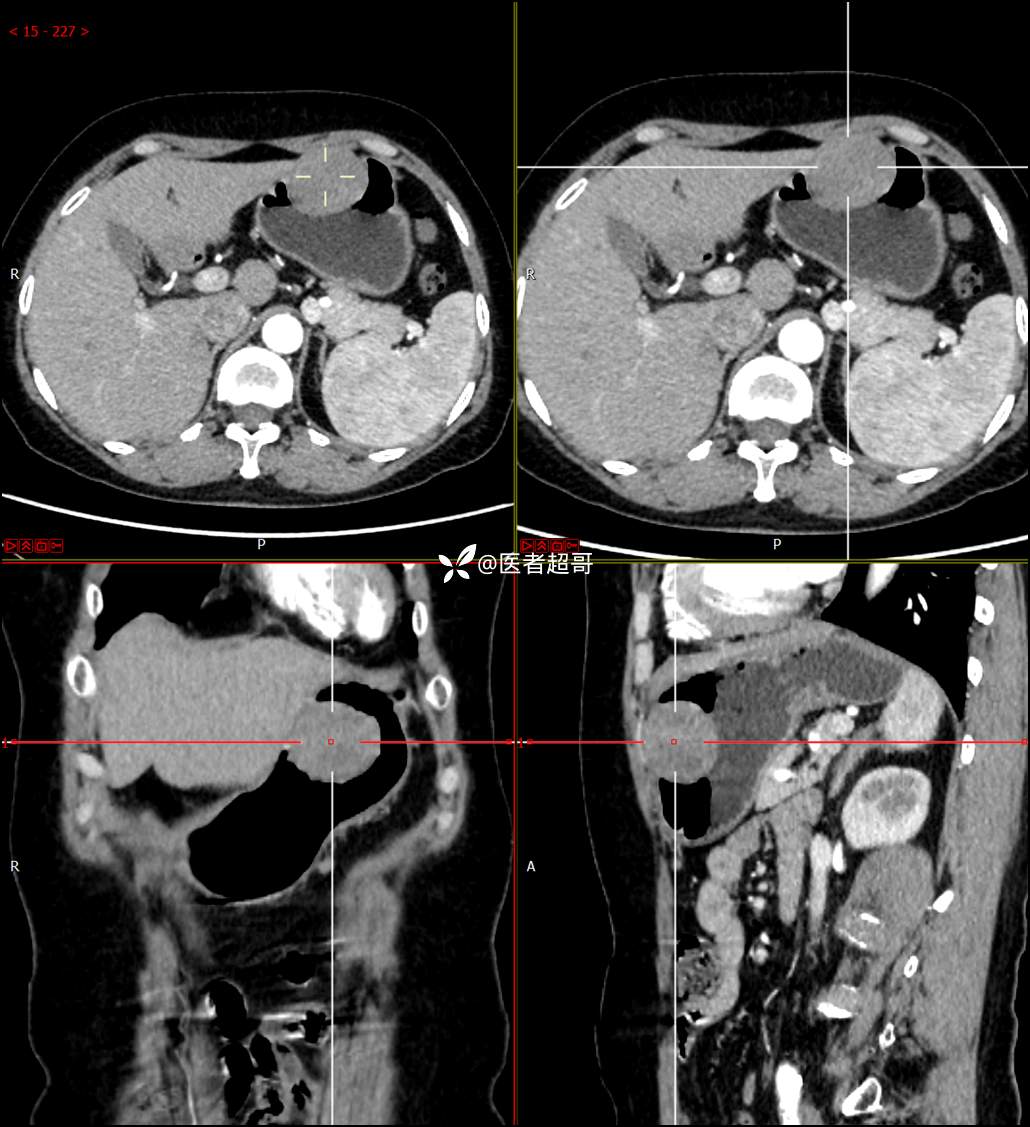

【影诊笔记759】胃体巨大隆起,间质瘤?神经鞘瘤?平滑肌瘤?请鉴别诊断!有结果!

患者半月前无明显原因及诱因出现上腹部疼痛不适,以夜间腹痛为主,无放射性疼痛,间断嗳气,无反酸烧心,无腹泻黑便,于我院门诊行胃镜显示:胃体前壁巨大隆起型病变。